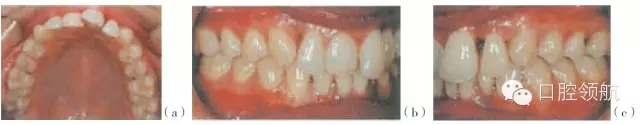

·菌斑生物膜會(huì)引起牙齦增生(圖29.2)。

圖29.2 (a~c)一個(gè)15歲的亞洲女孩,戴有固定矯治器,其菌斑控制得不好,前后牙區(qū)的牙齦發(fā)炎和腫脹